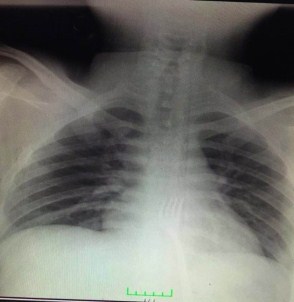

Konya’da zihinsel engelli 20 yaşındaki bir gencin yuttuğu 15 santimetrelik metal çatal, gerçekleştirilen ameliyatla midesinden çıkarıldı.

Ameliyatı gerçekleştiren Prof. Dr. Mehmet Erikoğlu, acil servise başvuran hastanın çatal yuttuğunun söylenmesi üzerine gerekli tetkikleri yaptıkların ve ardından hastayı hemen ameliyata aldıklarını söyledi.

Erikoğlu, mideden küçük bir kesi ile 15 santimetre boyundaki çatalı bulunduğu yerden çıkardıklarını ifade etti.